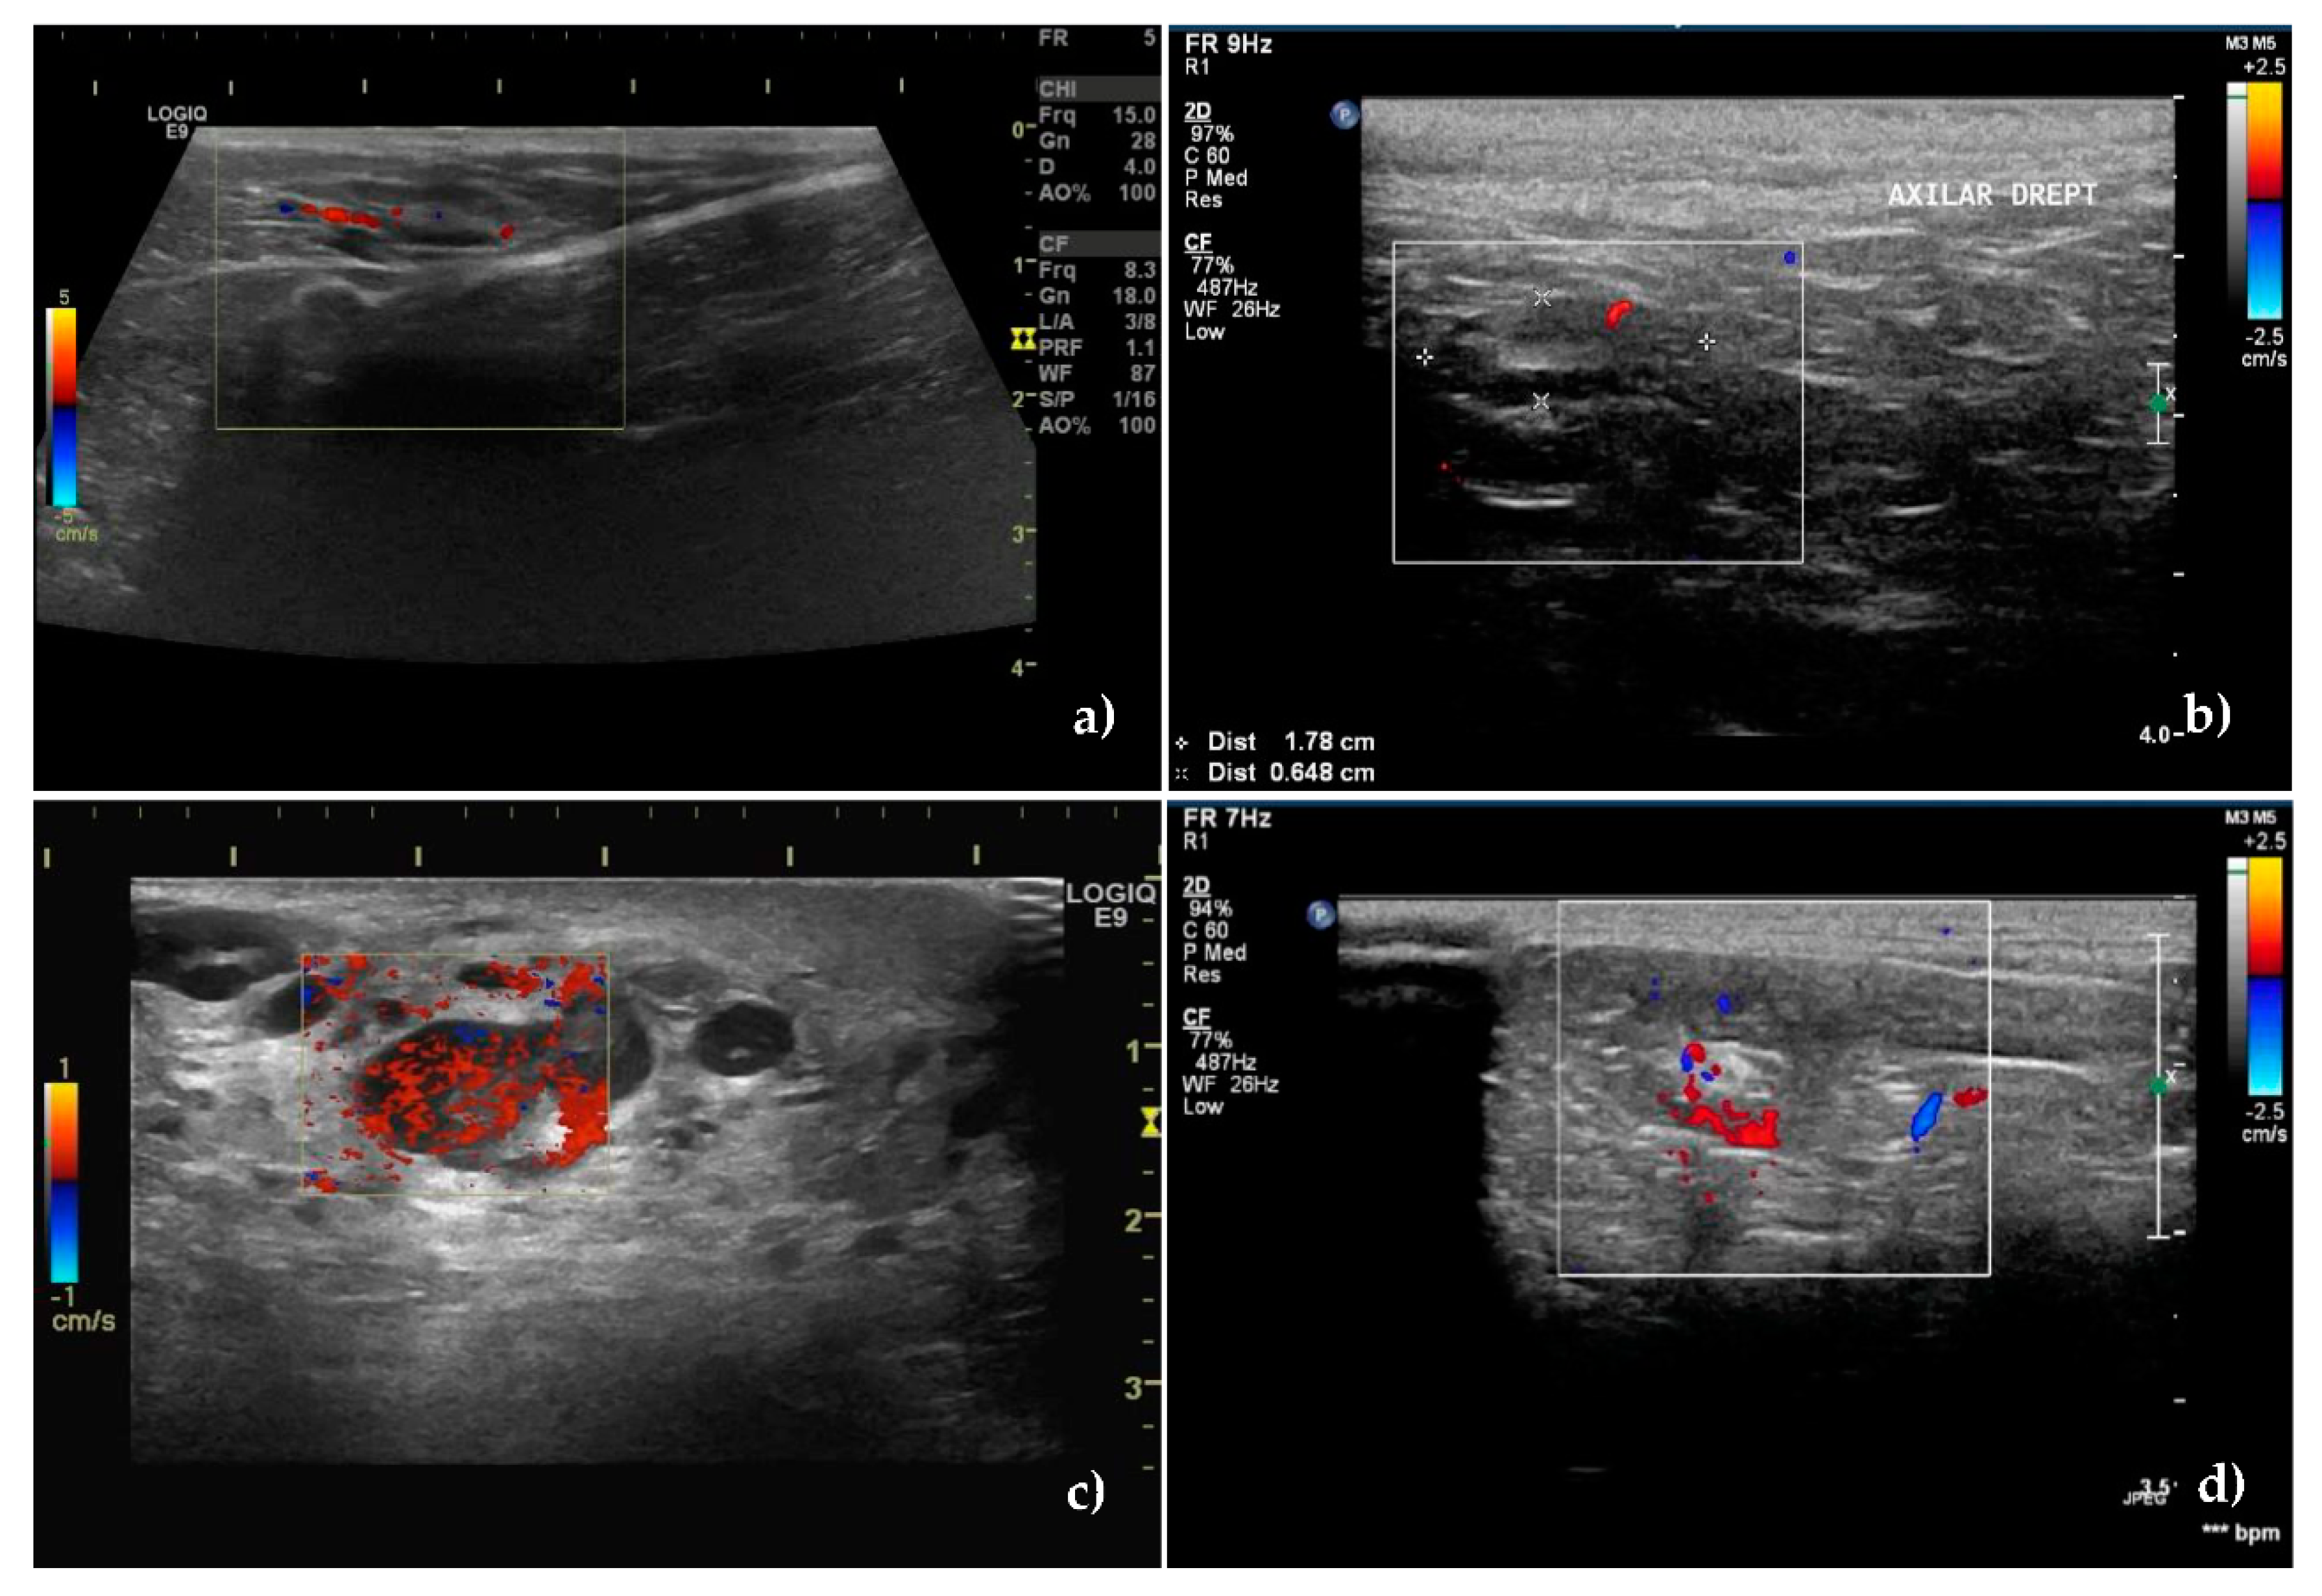

3.2. Color Doppler Ultrasonography

| COLOR DOPPLER ULTRASONOGRAPHY—VASCULAR PATTERN | |||

| Localization | |||

| Absence of vascular signal | 2(4.76) | 1(1.85) | <0.001 |

| Hilar pattern | 36(85.71) | 12(22.22) | |

| Peripheral pattern | 1(2.38) | 30(55.55) | |

| Mixed | 3(7.14) | 11(20.37) | |

| Type and distribution | |||

| Ordered | 36(85.71) | 5(9.25) | <0.001 |

| Chaotic | 4(9.52) | 48(88.88) | |

| NA | 2(4.76) | 1(1.85) | |

| Intranodal vascular resistance (expressed by mean ± SD) | |||

| RI | 0.5060 ± 0.147 | 0.7011 ± 0.138 | <0.001 |

| PI | 0.9828 ± 0.223 | 1.2426 ± 0.259 | |